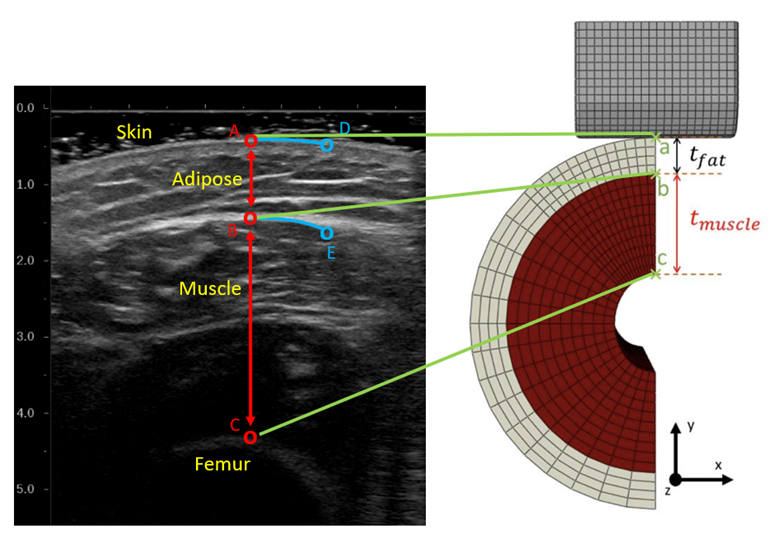

A combined experimental-numeric approach was used to perform the inverse optimization of the muscle and adipose properties. An indentation protocol using a custom ultrasound-force sensor setup was performed to extract the experimental force-displacement response of the muscle and adipose tissue. A simplified finite element model of the participant’s thigh which included both the muscle and adipose tissue was constructed which applied the loading of the ultrasound indentation on the thigh. An inverse optimization method which compared the experimental data to the numerical results of the participant’s model was used to identify the personalized muscle and adipose parameters. In this study, the authors’ modified the cost function associated with the optimization method to consider the impact of the changes in tissue morphology and its impact on identifying the material properties. To test the identifiability of the parameters, different starting points were tested in the algorithm. The results demonstrated that considering these new aspects in the cost function changed the descent and resulting parameters for the muscle and adipose tissue. Additionally, different starting points for initialing the algorithm resulted in different material properties for the soft tissue, which suggests the method has fallen into local minimums in its descent and has yet to identify a unique set of parameters of the muscle and adipose tissue of the participant.